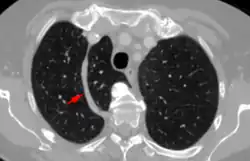

Azygos lobe in axial computertomography. Arrow on azygos vein.